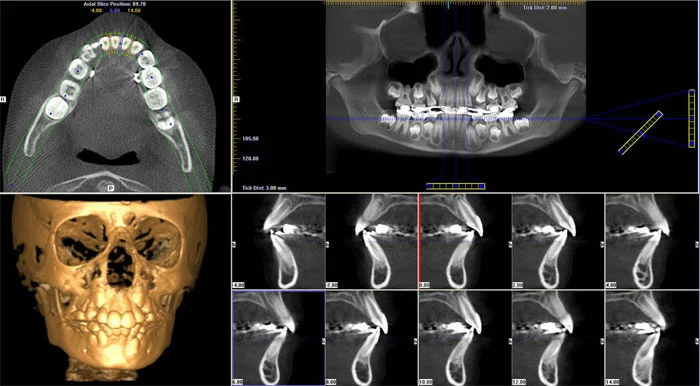

Dijital tomografi kemik kalınlığı, anatomik oluşumları (sinüs, sinir, damar vb.) kist, tümör gibi oluşumları en detaylı ve güvenli şekilde görmemizi sağlar. Üzerinde ölçüm yapmamıza olanak verir. Bu doğrultuda yapılan tedavinin kalitesi artar.

Dijital Tomografinin Avantajları Nelerdir?

- Dijital tomografi, klasik tomografilere kıyasla daha az radyasyon dozu içermektedir. Hasta sağlığı açısından daha az zararlıdır.

- Hızlı ve oldukça kolay bir görüntüleme yöntemidir.

- Dijital tomografinin görüntü kalitesi ve görüntü çözünürlüğü oldukça kaliteli olduğundan hasta tedavi planlamalarında en ince ayrıntılar da gözden kaçmaz.

- Derinlik ve hacim hesaplamaları dijital tomografi yardımıyla titizlikle yapılabilmektedir. Yumuşak doku kalınlığı ve kemik yoğunluğu ölçümü gibi hesaplamalar hasta tedavisi öncesinde hatasız planlanabilir.